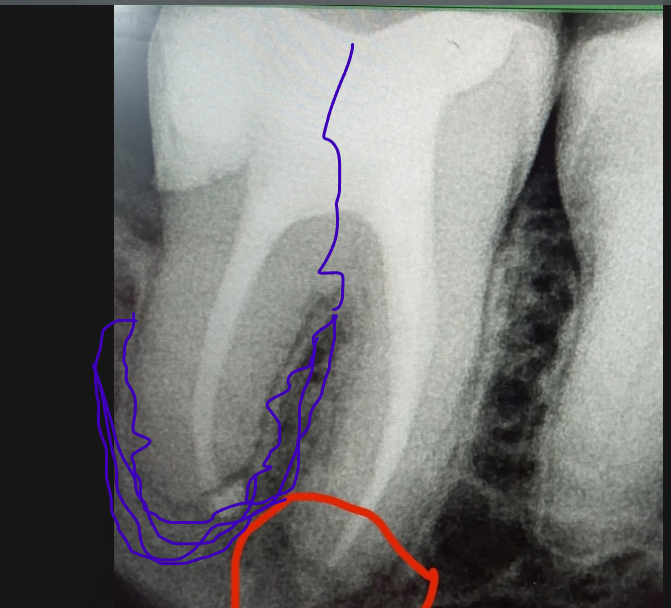

Pawa213123 Опубликовано 25 февраля, 2025 Поделиться Опубликовано 25 февраля, 2025 Зуб без нерва. Пол года назад делали снимок обычный + КТ. КТ показал, что в зубе нет инфекции. А на новом снимке вдруг что-то стало видно. Это артефакт какой-то или что? Я выделил это черным цветом. Ссылка на комментарий

Pawa213123 Опубликовано 25 февраля, 2025 Автор Поделиться Опубликовано 25 февраля, 2025 А если зуб расколется посередине, то от туда же пойдет воспаление (киста)? киста пойдет по пути, который я изобразил фиолетовым цветом, а не в челюстную кость, верно? Воспаление же идет по пути наименьшего сопротивления? Это я так, просто ради любопытства спрашиваю. А Ссылка на комментарий

Pawa213123 Опубликовано 25 февраля, 2025 Автор Поделиться Опубликовано 25 февраля, 2025 И вот это воспаление тоже пойдет не в кость, а либо по пути, который я снова изобразил фиолетовым, либо же в бока, чтобы образовать свищ, правильно? Ссылка на комментарий